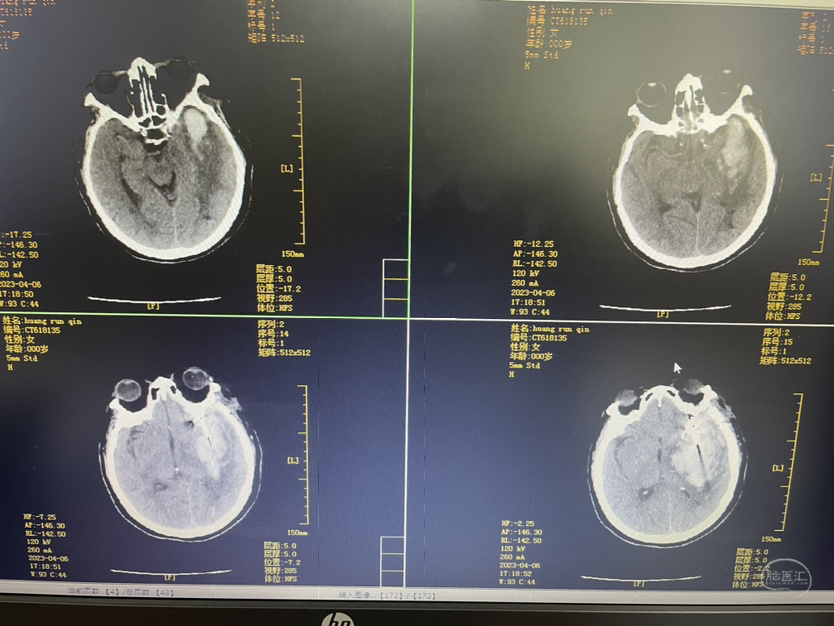

术后第一天

术后第三天

术后第五天

术后第十一天

术后第一个月

夹闭术后两个月,出院后一个月!再次出血,血肿量大,患者清醒!转上级市级医院,拟予介入栓塞后清除血肿